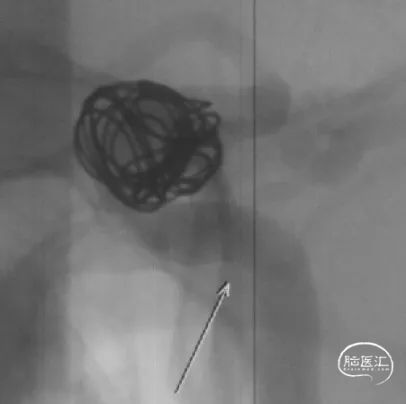

选用YonFlow®血流导向密网支架 4.75*30mm、弹簧圈 12×40,进行密网支架结合弹簧圈栓塞。

YonFlow®血流导向密网支架释放。

4、本例术中如何实现FD精准定位,是手术最困难的一个技术点。YonFlow®FD独创的100%可回收功能可实现支架从微导管完全推出后仍能回收至微导管重释放,同时输送系统支架近端/远端还带有定位Mark点,这些均可帮助医生在术中的安全释放、精确定位和方便调整,使支架释放位置至最佳,从而进一步提升手术精准度和效果,增加手术的成功率和安全性。